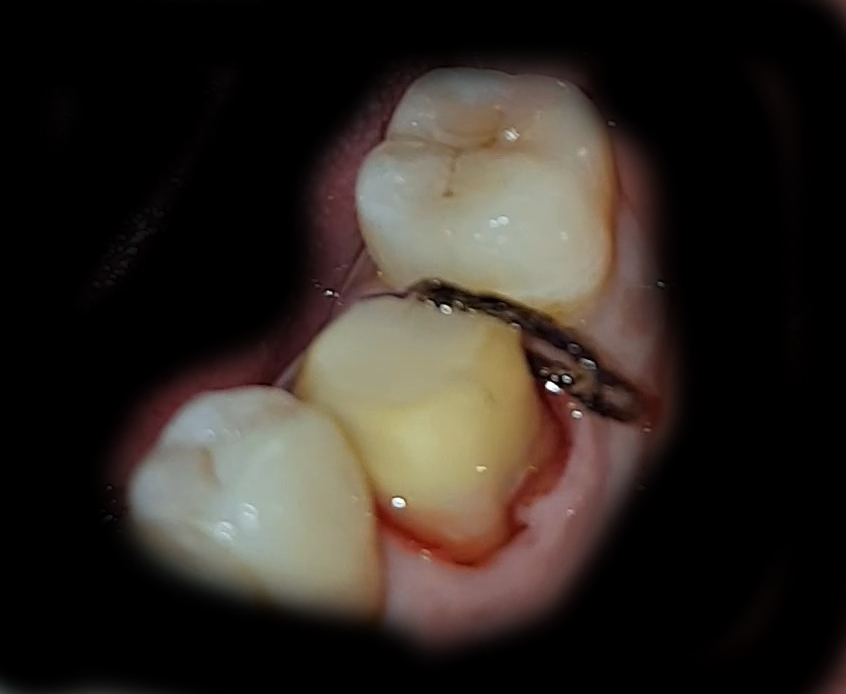

아래 이미지는 쪼금.. 살짝은.. 더러울 수 있으니...

비위가 약한 사람은 패스해라..

크라운을 씌우기 위해.. 신경 치료한 이빨을 갈아내었다..

뭐 치석이나... 썩은 부분 등.. 아주 싹다 작살내 버린 듯하다.(사진을 보니.... 더럽고 혐오스럽다..)

피도난다... 뭔 실로 무슨무슨 일을 처리하는 과정인데... 내가 모르니 설명을 못한다..

이후에 실을 빼고.. 또 먼가 하였는데... 기억이 나지 않는다..